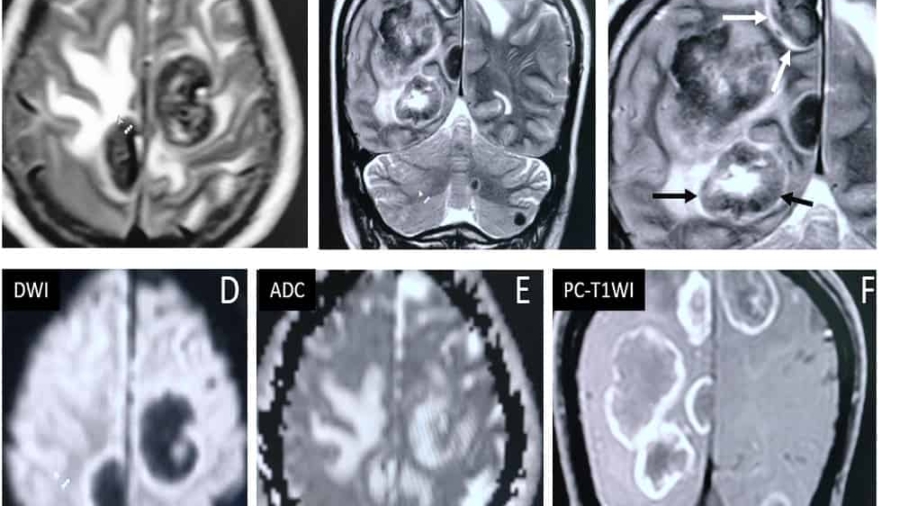

53 year old female presented with complains of gait imbalance and ataxia.

She has chronic kidney disease and was recently started on anti tubercular therapy(ATT) for pulmonary tuberculosis